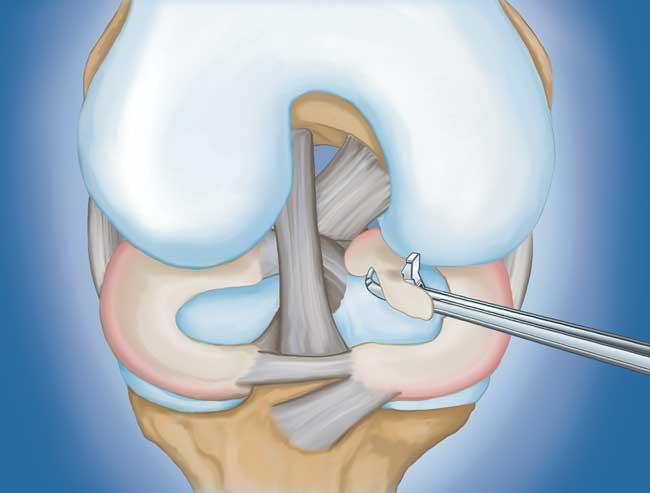

程序。 膝關(guān)節(jié)鏡檢查是最常進(jìn)行的外科手術(shù)之一。在這個(gè)過(guò)程中,外科醫(yī)生通過(guò)膝蓋上的一個(gè)小切口(入口)插入一個(gè)微型相機(jī)。這提供了膝蓋內(nèi)部的清晰視圖。然后外科醫(yī)生通過(guò)兩個(gè)或三個(gè)其他小入口插入手術(shù)器械以修剪或修復(fù)撕裂。

- 部分半月板切除術(shù)。 在這個(gè)過(guò)程中,受損的半月板組織被修剪掉。該程序通常允許在手術(shù)后立即負(fù)重和全方位運(yùn)動(dòng)。

在這段簡(jiǎn)短的手術(shù)視頻中,半月板部分切除術(shù)期間使用電動(dòng)剃須刀平滑了退行性半月板撕裂。

- 半月板修復(fù)。 一些半月板撕裂可以通過(guò)將撕裂的碎片縫合(縫合)在一起來(lái)修復(fù)。撕裂能否成功修復(fù)取決于撕裂的類型,以及受傷半月板的整體狀況。因?yàn)榘朐掳灞仨氁黄鹩希迯?fù)的恢復(fù)時(shí)間比半月板切除術(shù)長(zhǎng)。